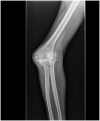

Anteroposterior radiograph of a patient with long-standing deformity of the elbow secondary to a childhood injury.